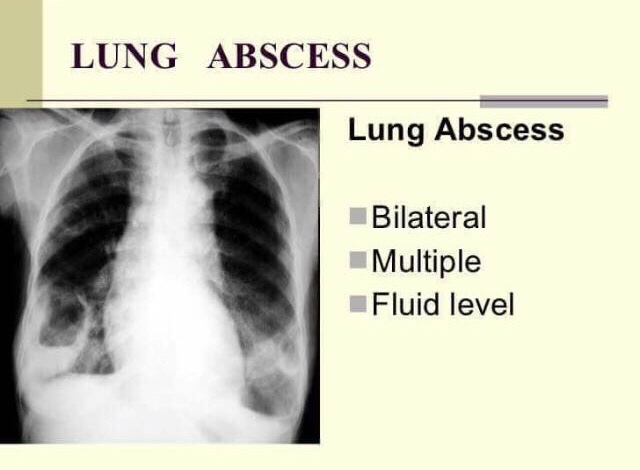

5) LUNG ABSCESS & CONSOLIDATION

➡️ Complications

- pleural collection

- cavitation